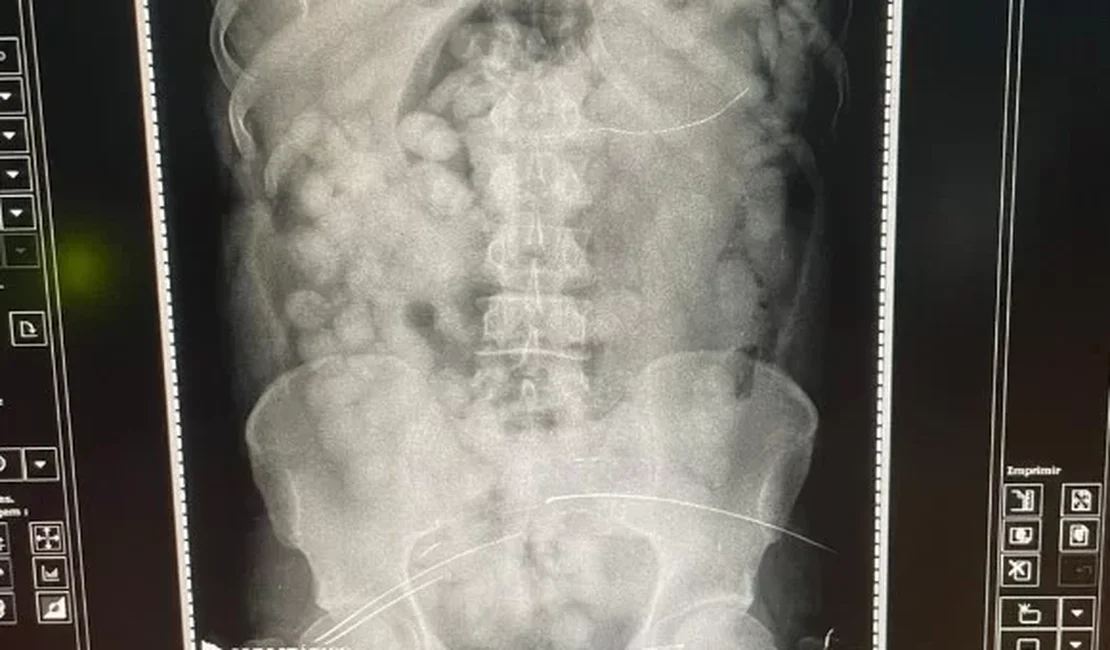

A Polícia Federal (PF) prendeu, nessa quinta-feira (7/9), um homem que tentou embarcar para Europa com mais de 100 cápsulas recheadas de cocaína no estômago.

O passageiro, venezuelano, foi abordado no Aeroporto Internacional de Belém e estava a caminho de Paris, na França. Ao ser flagrado no tráfico internacional de drogas, foi levado ao Pronto Socorro Municipal (PSM) para que pudesse expelir as cápsulas.

Ao ser entrevistado, o suspeito confessou que tinha engolido droga para levá-la na Europa. Com isso, foi levado ao Hospital da Aeronáutica de Belém para a retirada segura da droga.